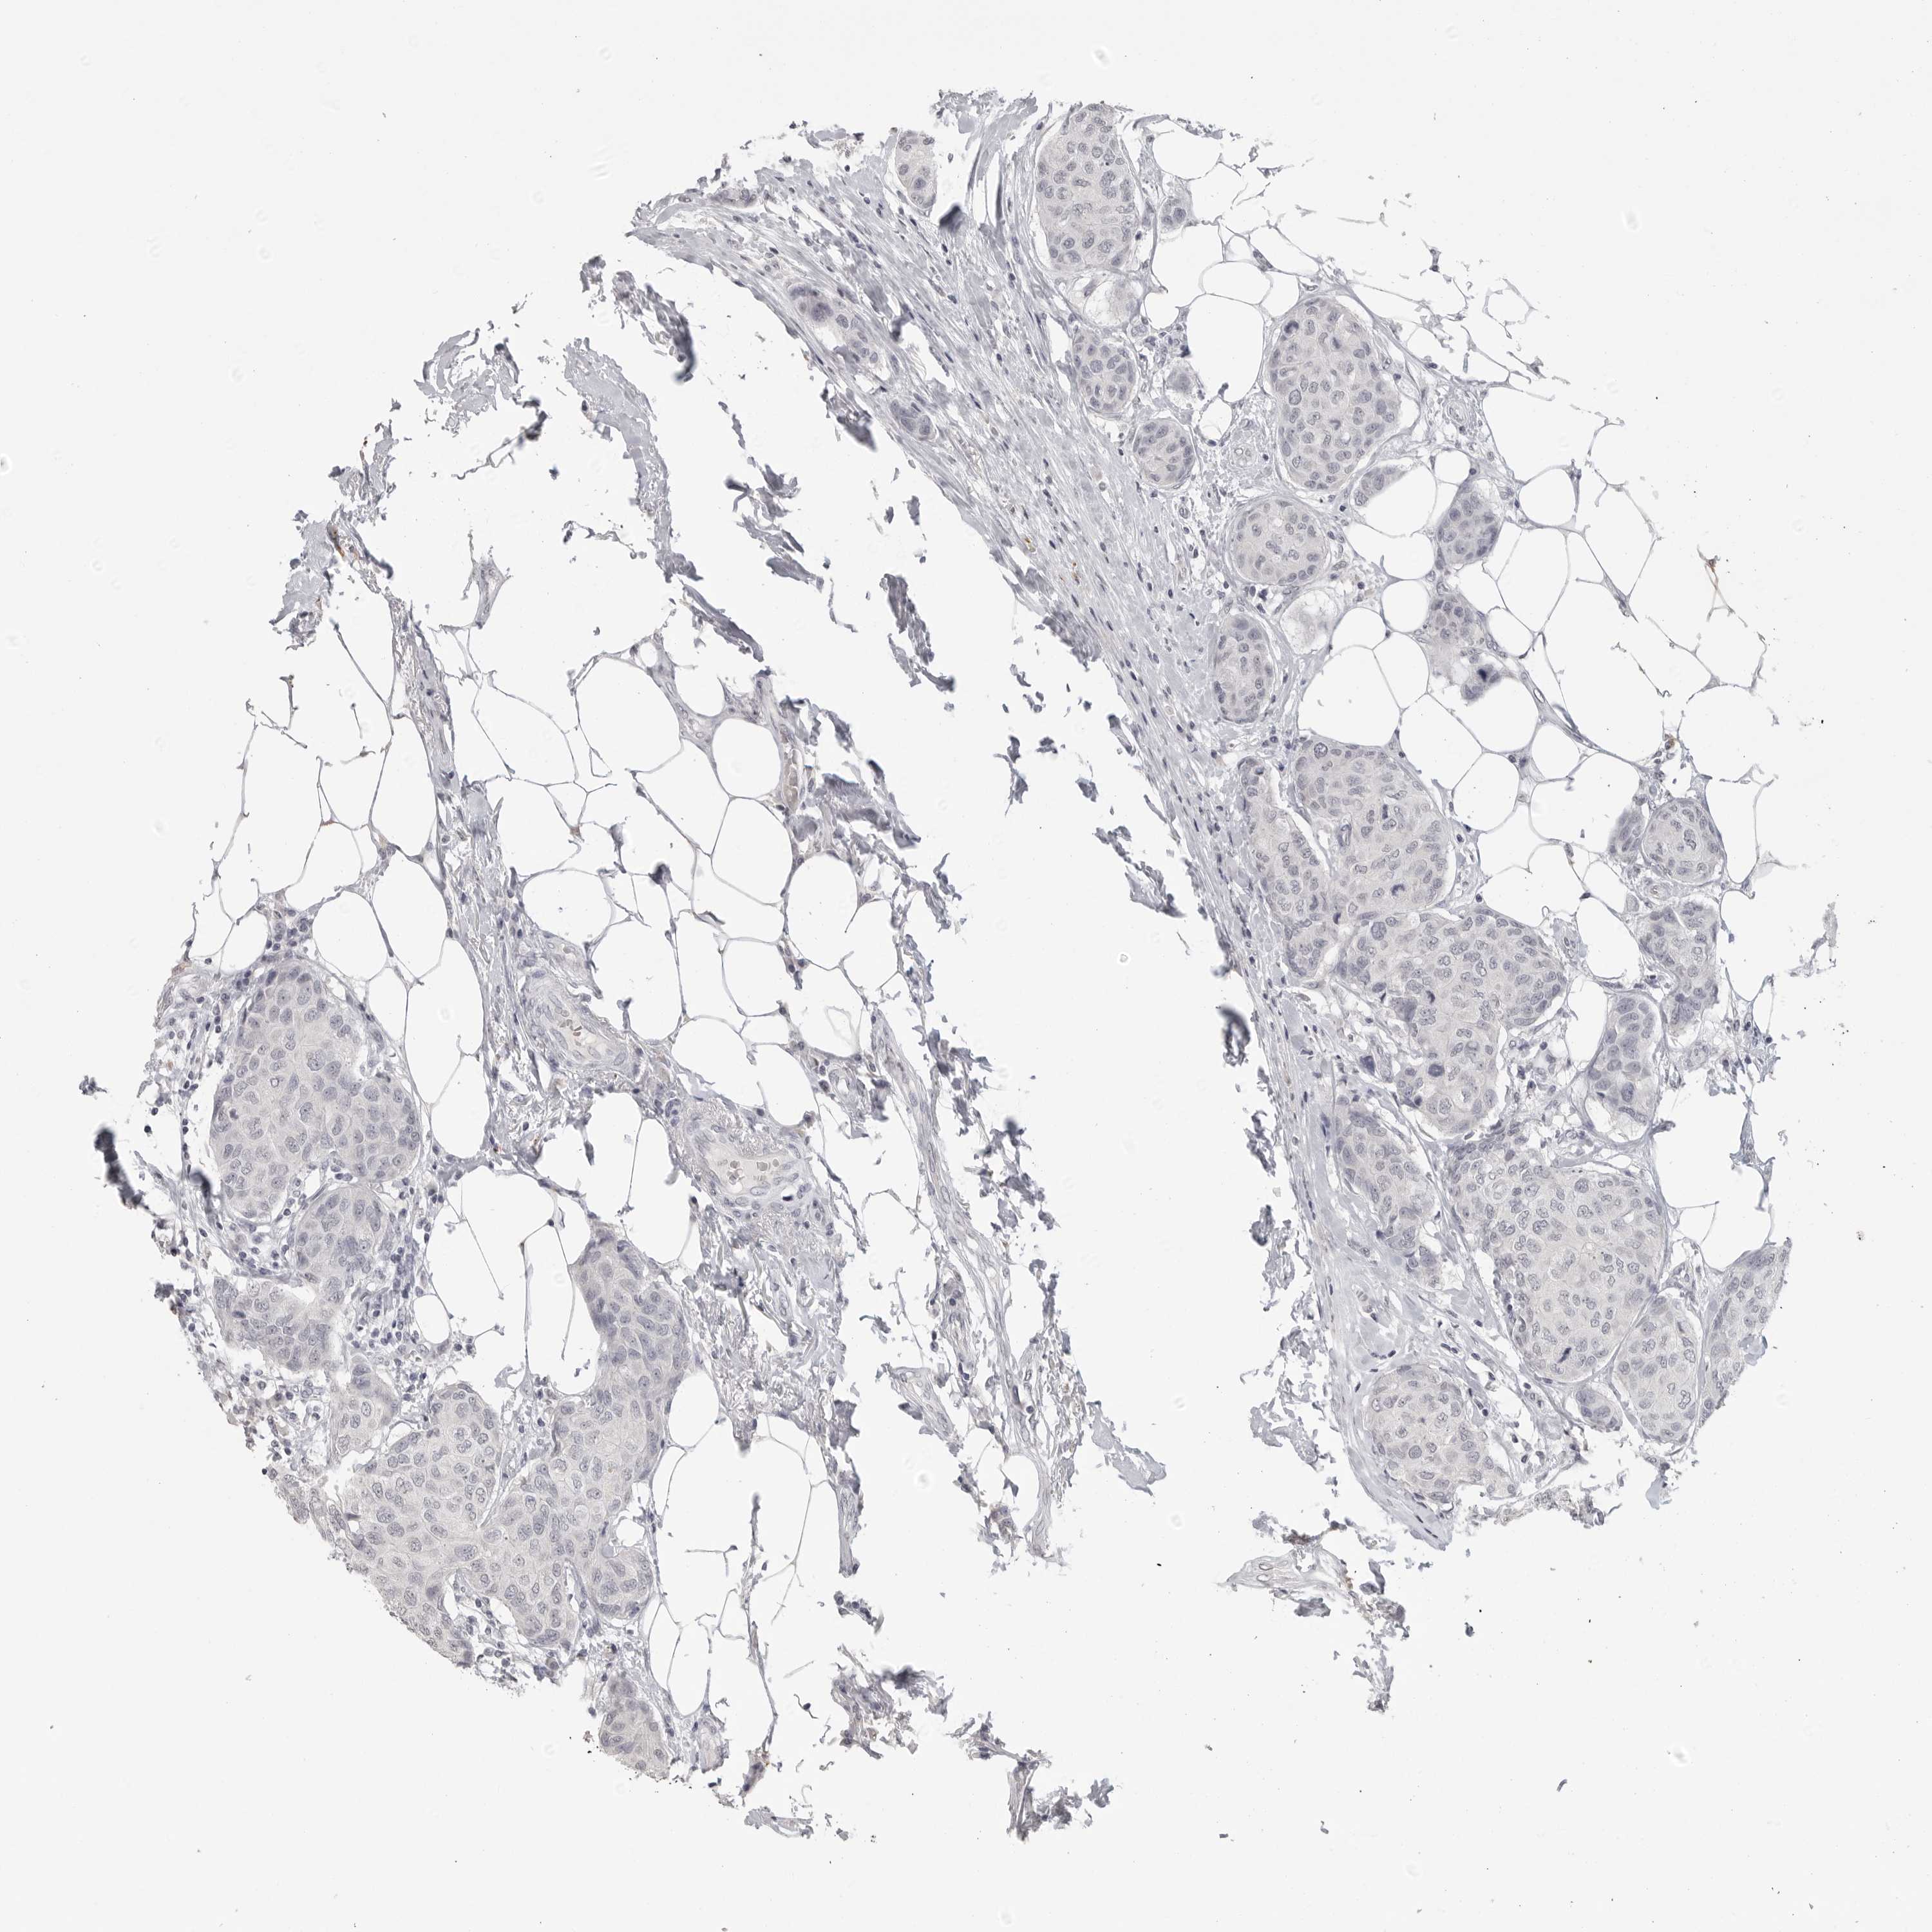

CANCER BREAST CANCER Show tissue menu

BRCA TCGA BRCA VALIDATION PROTEIN EXPRESSION